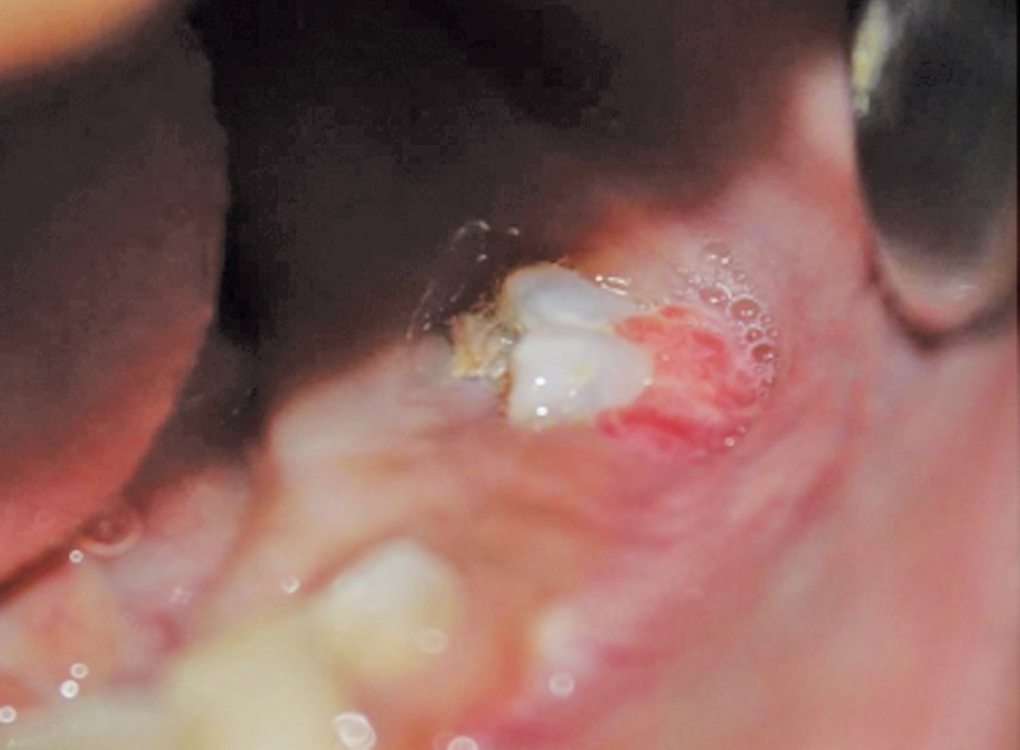

常见特征是骨脆性增加、高频率骨折、骨畸形和身材矮小等。脆骨病患者还可能出现其他临床症状,如牙齿脆性、蓝巩膜、听力下降、呼吸功能下降和心脏瓣膜反流。脆骨病的严重程度从轻微到极严重不等,最严重的形式是围产期死亡。

外观照

因此,患者可能有其他的体征和症状,包括蓝色巩膜、牙本质形成不全(DI)、听力障碍、过度松弛、脊柱侧弯和瘀伤和出血增加等。对此病的治疗尚需新技术方面的突破。